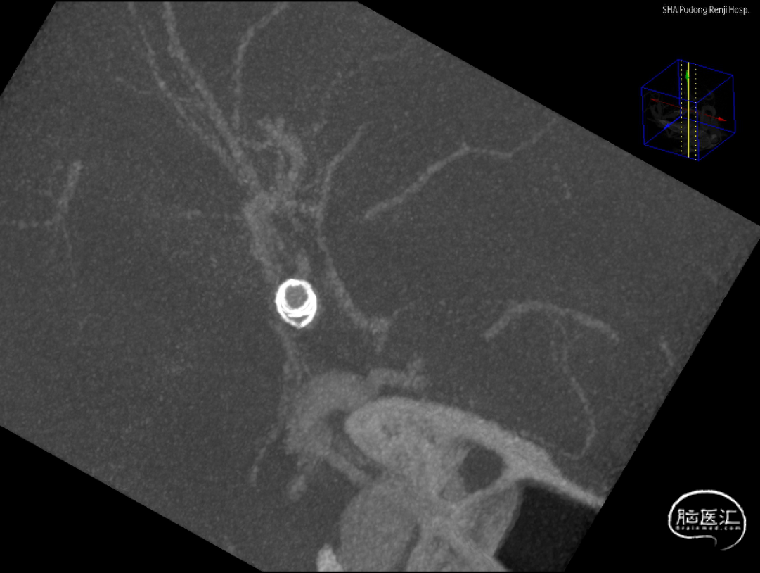

支架到位,原位释放,前段打开。

造影确认支架远端打开充分,贴壁良好,继续推送支架。

支架全部释放,调整张力,微导管通过支架,回收输送导丝。

支架内使用成襻微导丝进行按摩,使支架充分贴壁。

术后造影:支架充分覆盖动脉瘤瘤颈,贴壁良好,瘤体内可见造影剂滞留。

术后支架显影:定位精准,未覆盖颞前动脉及大脑前动脉。